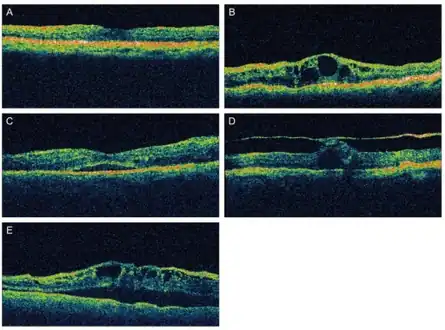

Different patterns of diabetic macular edema on optical coherence tomography a) Diffuse type of macular edema b) cystoid type of macular edema c) serous type of macular edema d) vitreomacular tractional type of macular edema e) mixed type of macular edema.